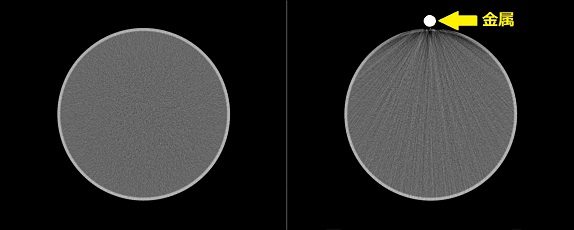

撮影部位に金属類がついた状態で撮影を行うとアーチファクトと呼ばれる障害陰影が画像上に現れてしまい,診断の妨げになってしまいます。そのため頭・頚部の検査ではヘアピン,ピアス,義歯などははずしていただきます。また,胸部や腹部等の検査ではブラジャーやファスナー,チャックなどが撮影時に写り込まないよう検査着に着替えてからの検査を推奨しています。

金属類の周りに黒い帯状の筋のように見えるものが金属アーチファクトです。図2では黄色い矢印で挟まれた部分(→ ←)に現れています。